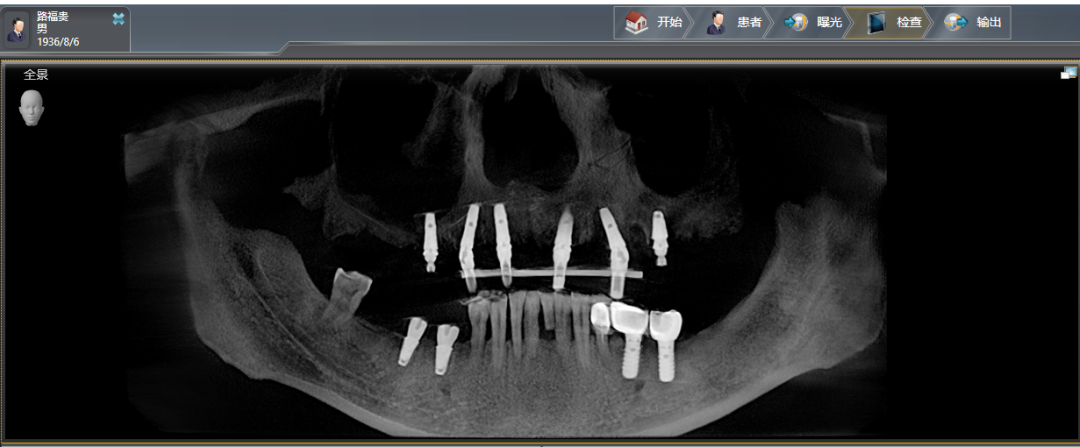

上车后看到姜书东90岁老母亲,也就是我的老亲家兰淑香也同去就诊,我们一起奔赴海德堡医院。找到德方院长森德博士、中方院长李志峰院长,当面会诊、拍摄全息X光照片,当面定下了手术方案。

2020年1月8日,我和90岁的老亲家先后动了手术。我的手术,上颌拔牙4个,同时打钛钢基钉6个,再安装12个牙冠,用时2个钟头;90岁的兰淑香打钢钉3个,不痛不肿,比我更顺利。

1月19日,我又在右下颌打进2颗钛钢钉,用时20分钟,一个月后再安装牙冠。